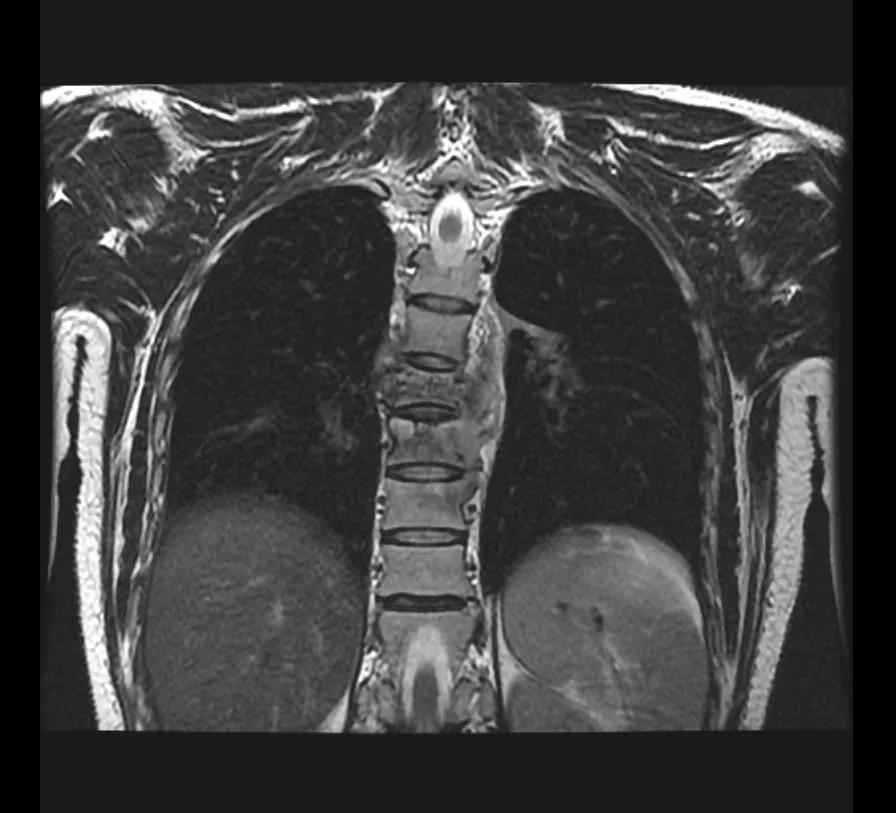

扎西来到成都新华医院骨科黄永红主任处就诊,CT核磁共振检查结果如黄主任所料扎西拉姆第6、7、8、9椎体被严重侵蚀,腰椎就好像被“吃掉了”;此外,椎体周围还形成了大量脓肿,对脊髓及神经造成压迫。

扎西的“脊椎结核”已经严重影响了脊柱的稳定性,“结核病灶在椎体内扩散,如不及时处理,会进一步侵犯脊椎椎体、椎管,压迫神经,进一步加重下肢乏力,甚至引起瘫痪、大小便失禁等后果”黄主任介绍。

手术必须尽快完成,但手术的难度也不小。由于结核病菌的侵蚀,扎西的脊椎体已经出现压缩塌陷、并压迫了椎管神经,手术需要在保护好脊髓和神经的前提下,切除病变的椎体;这个操作本身就存在非常高的神经损伤风险。